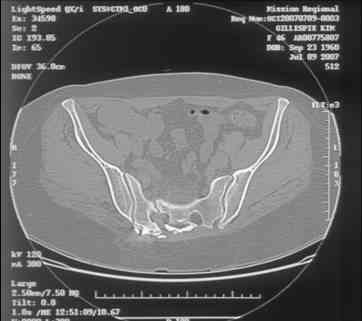

Re: Sacral Non-Union

Here is a magnified view. Sorry about the quality but the CT was scanned into our system.